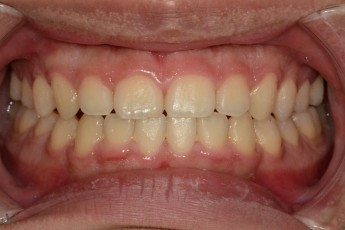

BEFORE & AFTER